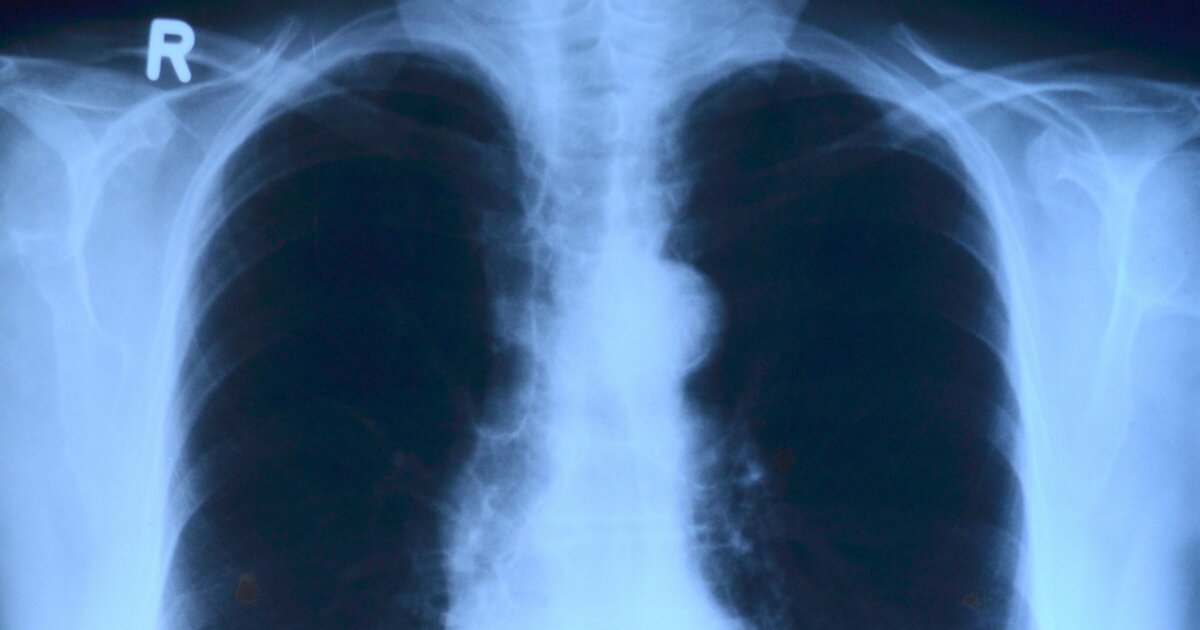

Фото с сайта pixabay.com

Газета The Daily Express рассказала историю Стаматиса Мораитиса — уроженца Греции, который прожил более четырех десятилетий после диагноза неизлечимого рака легких. Врачи в США, где он жил на тот момент, прогнозировали ему не более полугода жизни.

По данным издания, диагноз был поставлен, когда мужчине было около 60 лет. Лечение признали неэффективным, и Мораитис решил отказаться от медицинского вмешательства, вернувшись на остров Икария. Этот регион считается одной из «голубых зон», где продолжительность жизни значительно выше среднего.